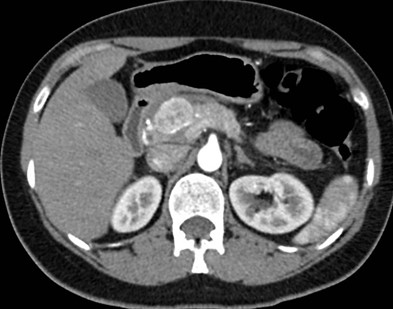

Tomografía de abdomen con cte ev: del 20/10/2023.

Complicaciones posquirúrgicas

Se le practica una duodeno pancreatectomía cefálica y triple anastomosis (hepato yeyuno, gastroentero y wirsung enteroanastomosis) el 12 de octubre de 2023 y pasa a internación UTI, el 14 de octubre se complica con fiebre, dolor abdominal y fístula pancreática con dosaje de amilasa de drenaje >6000, por lo que se le realiza tomografía que muestra abundante líquido libre en cavidad. Por tal motivo se le realiza una exploración quirúrgica por laparotomía, encontrándose abundante líquido + pancreatitis en la anastomosis yeyuno pancreática. Se realiza lavado de cavidad + 3 drenajes abocados a zona pancreática + yeyunostomia.

Paciente que se intuba y pasa a UTI, posteriormente extubación exitosa. El 22 de octubre se complica con colección abdominal, por lo cual requiere de drenaje percutáneo guiado por TC.